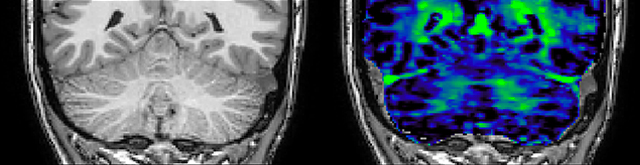

He says the accelerated scanning is achieved via the use of Compressed SENSE and MultiBand SENSE. “We can use Compressed SENSE acceleration factors of about 10 on a 3D FLAIR for instance, which is quite remarkable compared with what we saw with the Achieva. With 3D FLAIR, we can push the spatial resolution to 0.3 cubic mm and it works. Previously, our 3D FLAIR scans lasted about 8 minutes, but now with Elition they are five minutes. The SNR is also visibly better. Our SWI and QSM scans look fantastic. Also, since a lot of neuroimaging is EPI based, using the MultiBand SENSE technique can increase temporal resolution and make it possible to run complicated DTI scans relatively quickly.”

Sagittal 3D FLAIR with 0.3 mm3 voxel volume acquired in 5:12 min. using Compressed SENSE showing a (juxta)cortical MS lesion.

QSM based on a Compressed SENSE multi-echo SWI.